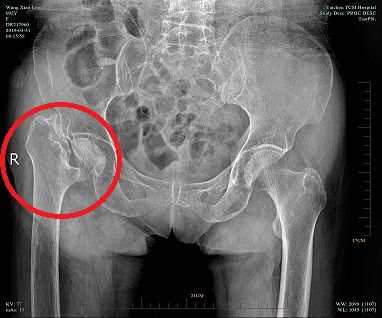

今年3月31日王阿婆在床邊再次摔倒,導(dǎo)致右髖疼痛加重,被子女送來我院就診,經(jīng)檢查后排除其他外傷性疾病,X片示:“右股骨頸陳舊性骨折,骨折頸部分缺失。”(具體見圖1)入住8樓骨三科,接診醫(yī)師丁志清看片后,再通過對阿婆的細(xì)致查體,認(rèn)為阿婆身體條件還不錯,建議行手術(shù)治療。

- 圖 1 -